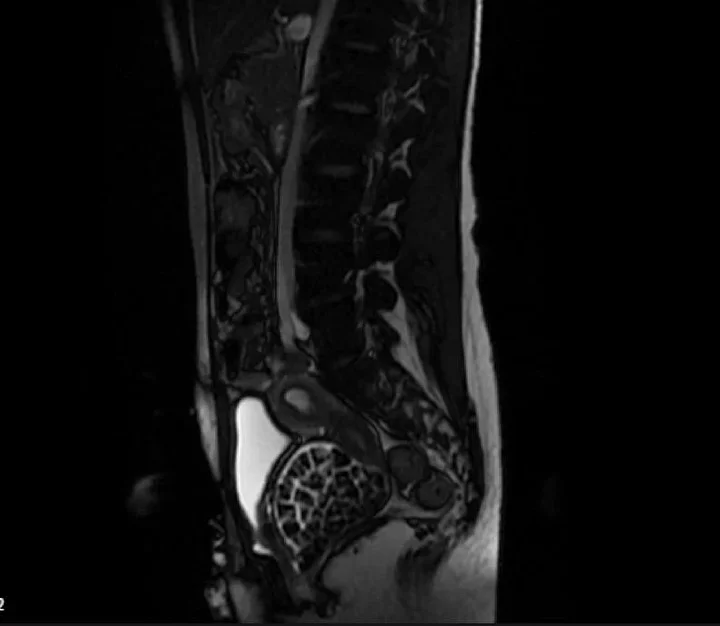

Hastasının durumuna yönelik konuşan Üroloji Uzmanı Doç. Dr. Erkan Erkan, "Hastamızın 2004 yılında doğduğunu ardından doğar doğmaz ekstrofi vezika dediğimiz 50 binde bir görülen bir anomaliden dolayı art arda ameliyatlar geçirdiğini öğrendik. 10 yaşında yine bir ameliyat geçirmişti, gerekli görüntüleme ve tetkiklerimizi yaptırdık. Normalde mesanesinin olması gereken yerin hemen arka kısmında taşlarla dolu bir kese olduğunu gördük, bunun üzerine ek görüntülemeler; MR çektirdik. Hastamız çelişkili açıklamalar almıştı, kendi radyolojik kliniğimiz ve edindiğimiz konsültasyonlarda taşların mesanede değil vajinal boşlukta oluştuğunu düşündük, bir planlama yaptık.

Kadın doğum hocamızın da çabasıyla taşları tamamen temizledik ardından ileride normal bir hayat sürmesi bakımından oraya plastik cerrahi yaptık. 287 adet taş çıkardık, pratikte gerçekten görünce çok şaşırdık çünkü bu aynı zamanda literatürde çok nadir görülen bir olay. Biz ameliyata hazırlanırken de teorik olarak biraz araştırdık. Literatürde gördüğümüz kadarıyla buna benzer bu tanıma uyan bir vaka vardı. Literatürde sanırım yayınlanmış 2’nci vaka olacak. Farkındalık çok önemli, bilinçli bir hastamız vardı. Doğumsal anomaliyle doğan çocuklarımızda ileride bunlara bağlı bazı sıkıntılar çıkabileceğinin öngörülmesi lazım. İlgili tedavilerini alsalar bile düzenli takiplere gelmeleri gerekiyor. İleride eğer dikkat etmezse ki zannetmiyorum, tekrarlayabilir. Bu rahatsızlık ekstrofi vezikal epispadias durumu çok nadir bir durum" dedi.

Genç kızın uzun süredir devam eden karın ağrısı olduğunu söyleyerek sözlerine başlayan Jinekolojik Onkoloji Uzmanı Op. Dr. Emin Erhan Dönmez, "Mesane taşları olduğu düşünülerek daha büyük bir hastaneye refere edilmiş. Aramızda mini bir konsey yaparak muayene ettik. Vajen bir hazne görevi görerek orada durağan bir idrar, uzun süre beklediği için idrar içindeki minerallerde çökerek taşlar oluşmuş. Mesanedeki idrarın vajene akmış olabileceği ve vajende göllenen idrar nedeniyle taşların burada oluşacağını düşündük, ameliyatımızı planladık. Ameliyata tanı amaçlı girmiştik, sistoskopi (Mesane gibi idrar yollarını kapsayan kısımlardaki rahatsızlıkların teşhis ve tedavisinde kullanılan endoskopik bir yöntem) dediğimiz ameliyatı Erkan Hocam ile birlikte gerçekleştirdik.

Önce mesaneyi bir görüntüledik, mesane tabanına yaklaşık 2-3 cm’lik bir alandan vajene fistülize olduğunu gördük. Mesaneden vajene geçtiğimiz esnada tüm vajenin taşlarla dolu olduğunu gördük. Tanı amacıyla girdiğimiz ameliyatta her şey de olağan gittiği için tedaviye geçtik. Taşların çıkabileceği kadar bir genişlik sağladık. Daha sonra yaklaşık en büyüğü 2,5 cm boyutlarında olan, irili ufaklı 287 tane taşı ameliyat esnasında çıkarmış olduk. Taşların tekrarlamaması için idrarın göllenmemesi, en azından dışarıya rahatça boşalabilmesi için vajinal rekonstrüksiyonu sağladık. Ameliyatta da herhangi bir problem yaşamadık. Literatürü Erkan Hocam ile birlikte değerlendirmiştik. Primer olarak vajende birikmiş olan bu kadar çok sayıda taşla ilgili bir makale görmedik, rastlamadık" dedi.